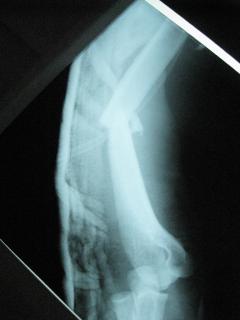

Περίπτωση 4ου ασθενούς

Τα εν λόγω κατάγματα είναι αρκετά συνηθισμένα και συχνά συμβαίνουν μετά από τροχαία ατυχήματα ή πτώση από ύψος. Παρατηρείται εξαιρετικά μεγάλη ποικιλία στη μορφή τους, κατα κανόνα όμως είναι σοβαρά και πολλές φορές ανοικτά – δηλ με τραύμα στο σημείο του κατάγματος – κάτι που αυξάνει τον κίνδυνο λοίμωξης και επιβαρύνει την πορεία της θεραπείας. Στα κατάγματα των άνω άκρων ενδέχεται να υπάρξει και τραυματισμός νεύρων, που χρειάζεται επίσης αντιμετώπιση.

Με τα σύγχρονα μέσα που διαθέτουμε, όλα σχεδόν αυτά τα κατάγματα πρέπει να αντιμετωπίζονται χειρουργικώς. Υπάρχει πληθώρα υλικών οστεοσύνθεσης (πλάκες διαφόρων τύπων, ενδομυελικοί ήλοι, συστήματα εξωτερικής οστεοσύνθεσης) που είναι διαθέσιμα και επαφίεται στην εμπειρία του χειρουργού η επιλογή.

Φυσικά το τελικό αποτέλεσμα θα εξαρτηθεί εν πολλοίς από τον τύπο του κατάγματος και την δεινότητα του χειρουργού.

Όλες οι φωτογραφίες ολες προέρχονται από το προσωπικό αρχείο του κου Μ. Τυλλιανάκη